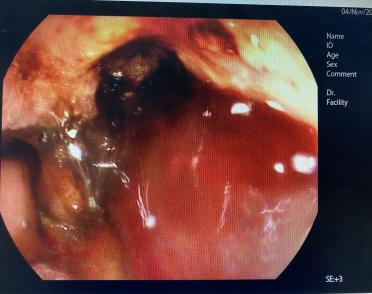

胃镜:贲门下方、胃体前壁、胃体小弯侧、胃体后壁见巨大溃疡性肿物,考虑胃癌并出血。

图2.胃镜